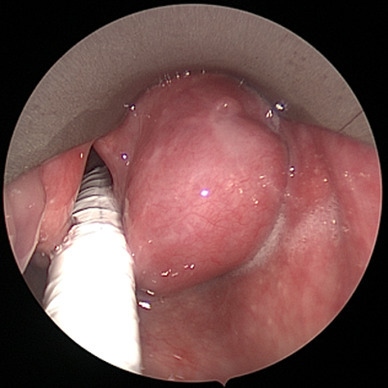

The patient underwent a microlaryngoscopy under general anaesthetic. The mass appeared to be pedicled on the right aryepiglottic fold and the medial wall of the right piriform fossa. A 3 cm submucosal lobulated soft mass was excised using Co2 laser (Sharplan) set on 4 W, continuous wave in super-pulse mode under microscopic vision with a focal length of 400 mm. (Fig. 2). The postoperative period was uneventful and the patient was discharged on the day of the operation with improved motility of the right vocal cord.

Fig. 2.

Endoscopic photograph of laryngeal mass in the right piriform fossa taken at the time of surgery